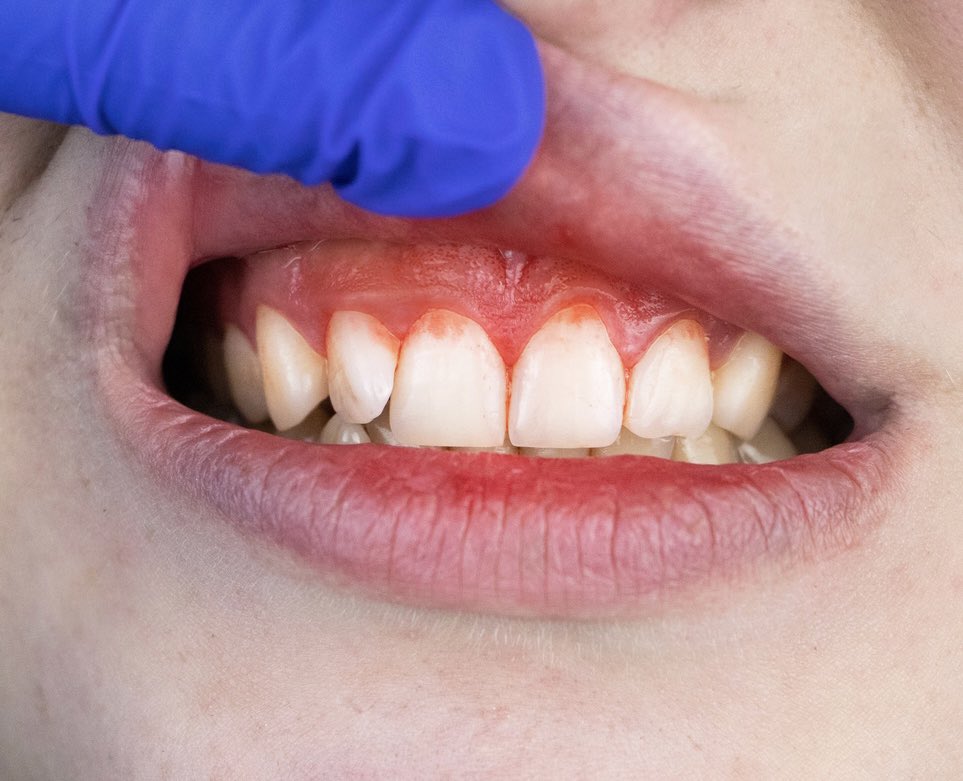

بعد إزالة الخيط من الأسنان و حصلته متقطع ممكن يكون عندك تسوس أو يكون لديك حشوة تحتاج لتبديل، وأذا كان عندك دم شديد بعد الخيط معناه عندك إلتهاب لثة لازم ترجع لطبيبك بكل الحالتين..